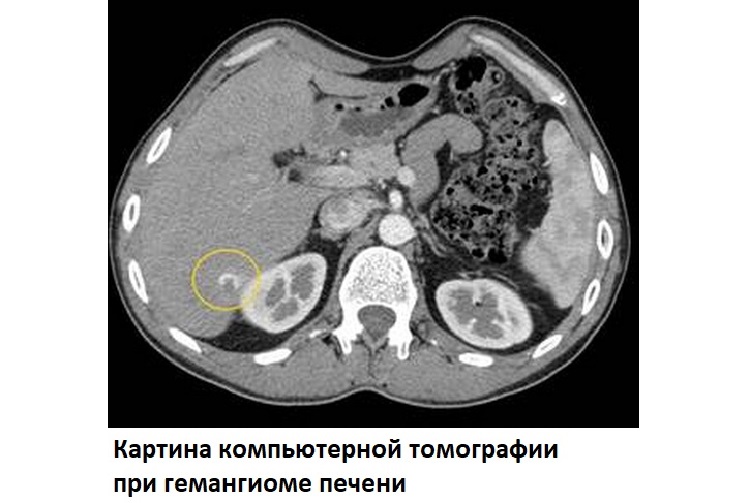

- КТ, МРТ (компьютерная и магнитно-резонансная томография).

Методики томографии также информативны. Гемангиома печени на МРТ выглядит как дольчатое образование с перегородками, имеющее ровные очертания. Тесты КТ лучше проводить с использованием контрастирования – то есть введения специальных веществ, накапливающихся в опухоли и позволяющих выделить ее на снимке среди иных участков ткани.